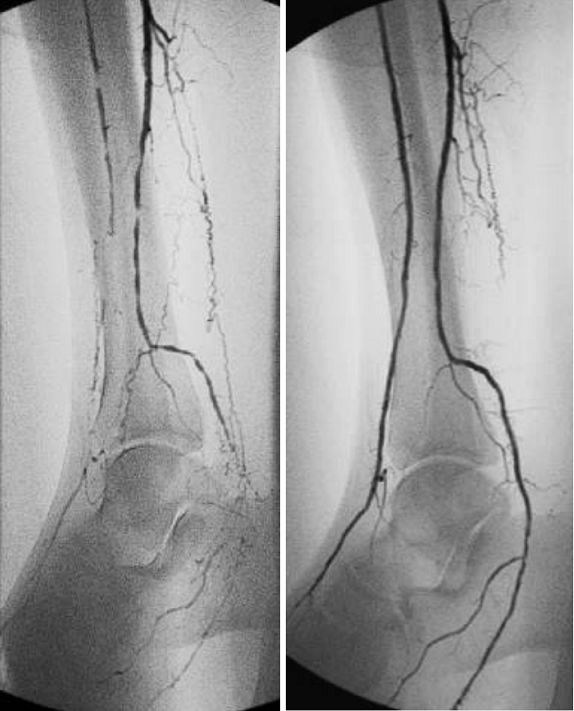

糖尿病下肢血管介入手术成功率,糖尿病下肢麻木中医辨证分析

介入治疗前后下肢血管对比图